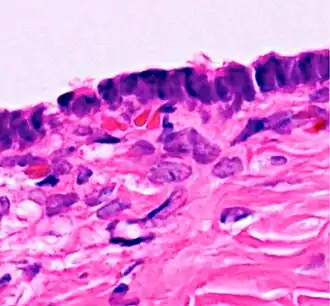

Histopathology

In case an ovarian cyst is surgically removed, a more definite diagnosis can be made by histopathology:

Type Subtype Typical microscopy findings Image

Cystadenoma Serous cystadenoma Cyst lining consisting of a simple epithelium, whose cells may be either:[26]

• columnar and tall and contain cilia, resembling normal tubal epithelium

• cuboidal and have no cilia, resembling ovarian surface epithelium

Mucinous cystadenoma Lined by a mucinous epithelium